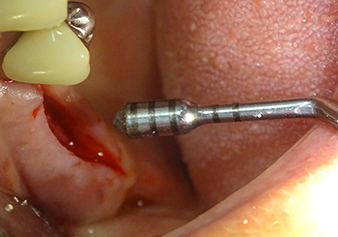

Après un contrôle intermédiaire (Fig. 4), une étape de préparation ultérieure est exécutée (Fig. 5). Puis on utilise l’insert Z35P hydraulique pour relever la membrane vers la position souhaitée (Fig. 6 et 7). Ensuite, une préparation piézochirurgicale supplémentaire est pratiquée sur le site implantaire, en utilisant pour terminer un burin rotatif et une fraise à épaulement jusqu’à 4,8 mm de diamètre d'implant. Avant l’insertion de l'implant, le matériau d’augmentation (taille de particules env. 0,8-1,6 mm) est introduit sous la membrane de Schneider (Fig. 8).